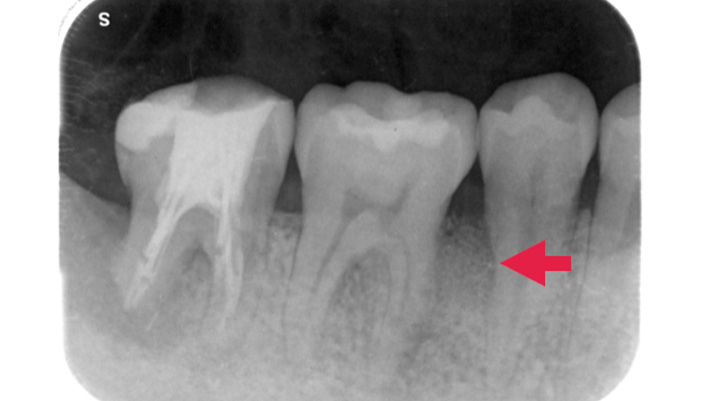

治療前

患者様は「根管治療中に器具が折れたと言われた」とのことで来院されました。診査の結果、根管内に破折したファイルが残存している状態が確認されました。CTで破折ファイルの位置や周囲の状態を詳しく確認したうえで、拡大視野下にて慎重に除去を行いました。

| 主訴 | 他院で治療しているが、治らない。 |

|---|---|

| 治療期間 | 1ヶ月 |

| 治療費 | 保険適応 |

| 治療内容 | 治療中に折れた器具(破折ファイル)があり、折れた器具の先が感染していて痛みがあったため、折れた器具を取り根管治療をしたケースです。 |

| 治療のリスク | 折れた器具が取れないこともあります。 |